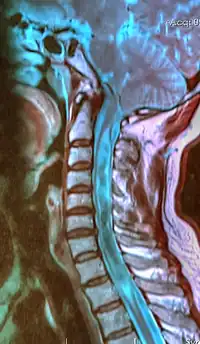

![]() | |

| A sagittal FLAIR MRI scan, from a patient with an Arnold–Chiari malformation, demonstrating tonsillar herniation of 7 mm. | |

Diagnosis is made through a combination of patient history, neurological examination, and medical imaging.[23][24] Magnetic resonance imaging (MRI) is considered the preferred imaging modality for Chiari malformation.[25] The MRI visualizes neural tissue such as the cerebellar tonsils and spinal cord as well as bone and other soft tissues. CT and CT myelography are other options and were used prior to the advent of MRI, unfortunately the resolution of CT based modalities do not characterize syringomyelia and other neural abnormalities as well.[26]

By convention, the cerebellar tonsil position is measured relative to the basion-opisthion line, using sagittal T1 MRI images or sagittal CT images.[27] The selected cutoff distance for abnormal tonsil position is somewhat arbitrary, as not every person will be symptomatic at a certain amount of tonsil displacement, and the probability of symptoms and syrinx increases with greater displacement; however, greater than 5 mm is the most frequently cited cutoff number, though some consider 3–5 mm to be "borderline"; pathological signs and syrinx may occur beyond that distance.[27][28][29] One study showed little difference in cerebellar tonsil position between standard recumbent MRI and upright MRI for patients without a history of whiplash injury.[22] Neuroradiological investigation is used to first rule out any intracranial condition that could be responsible for tonsillar herniation. Neuroradiological diagnostics evaluate the severity of crowding of the neural structures within the posterior cranial fossa and their pressure against the foramen magnum. Chiari 1.5 is a term used when both brainstem and tonsillar herniation through the foramen magnum are present.[30]